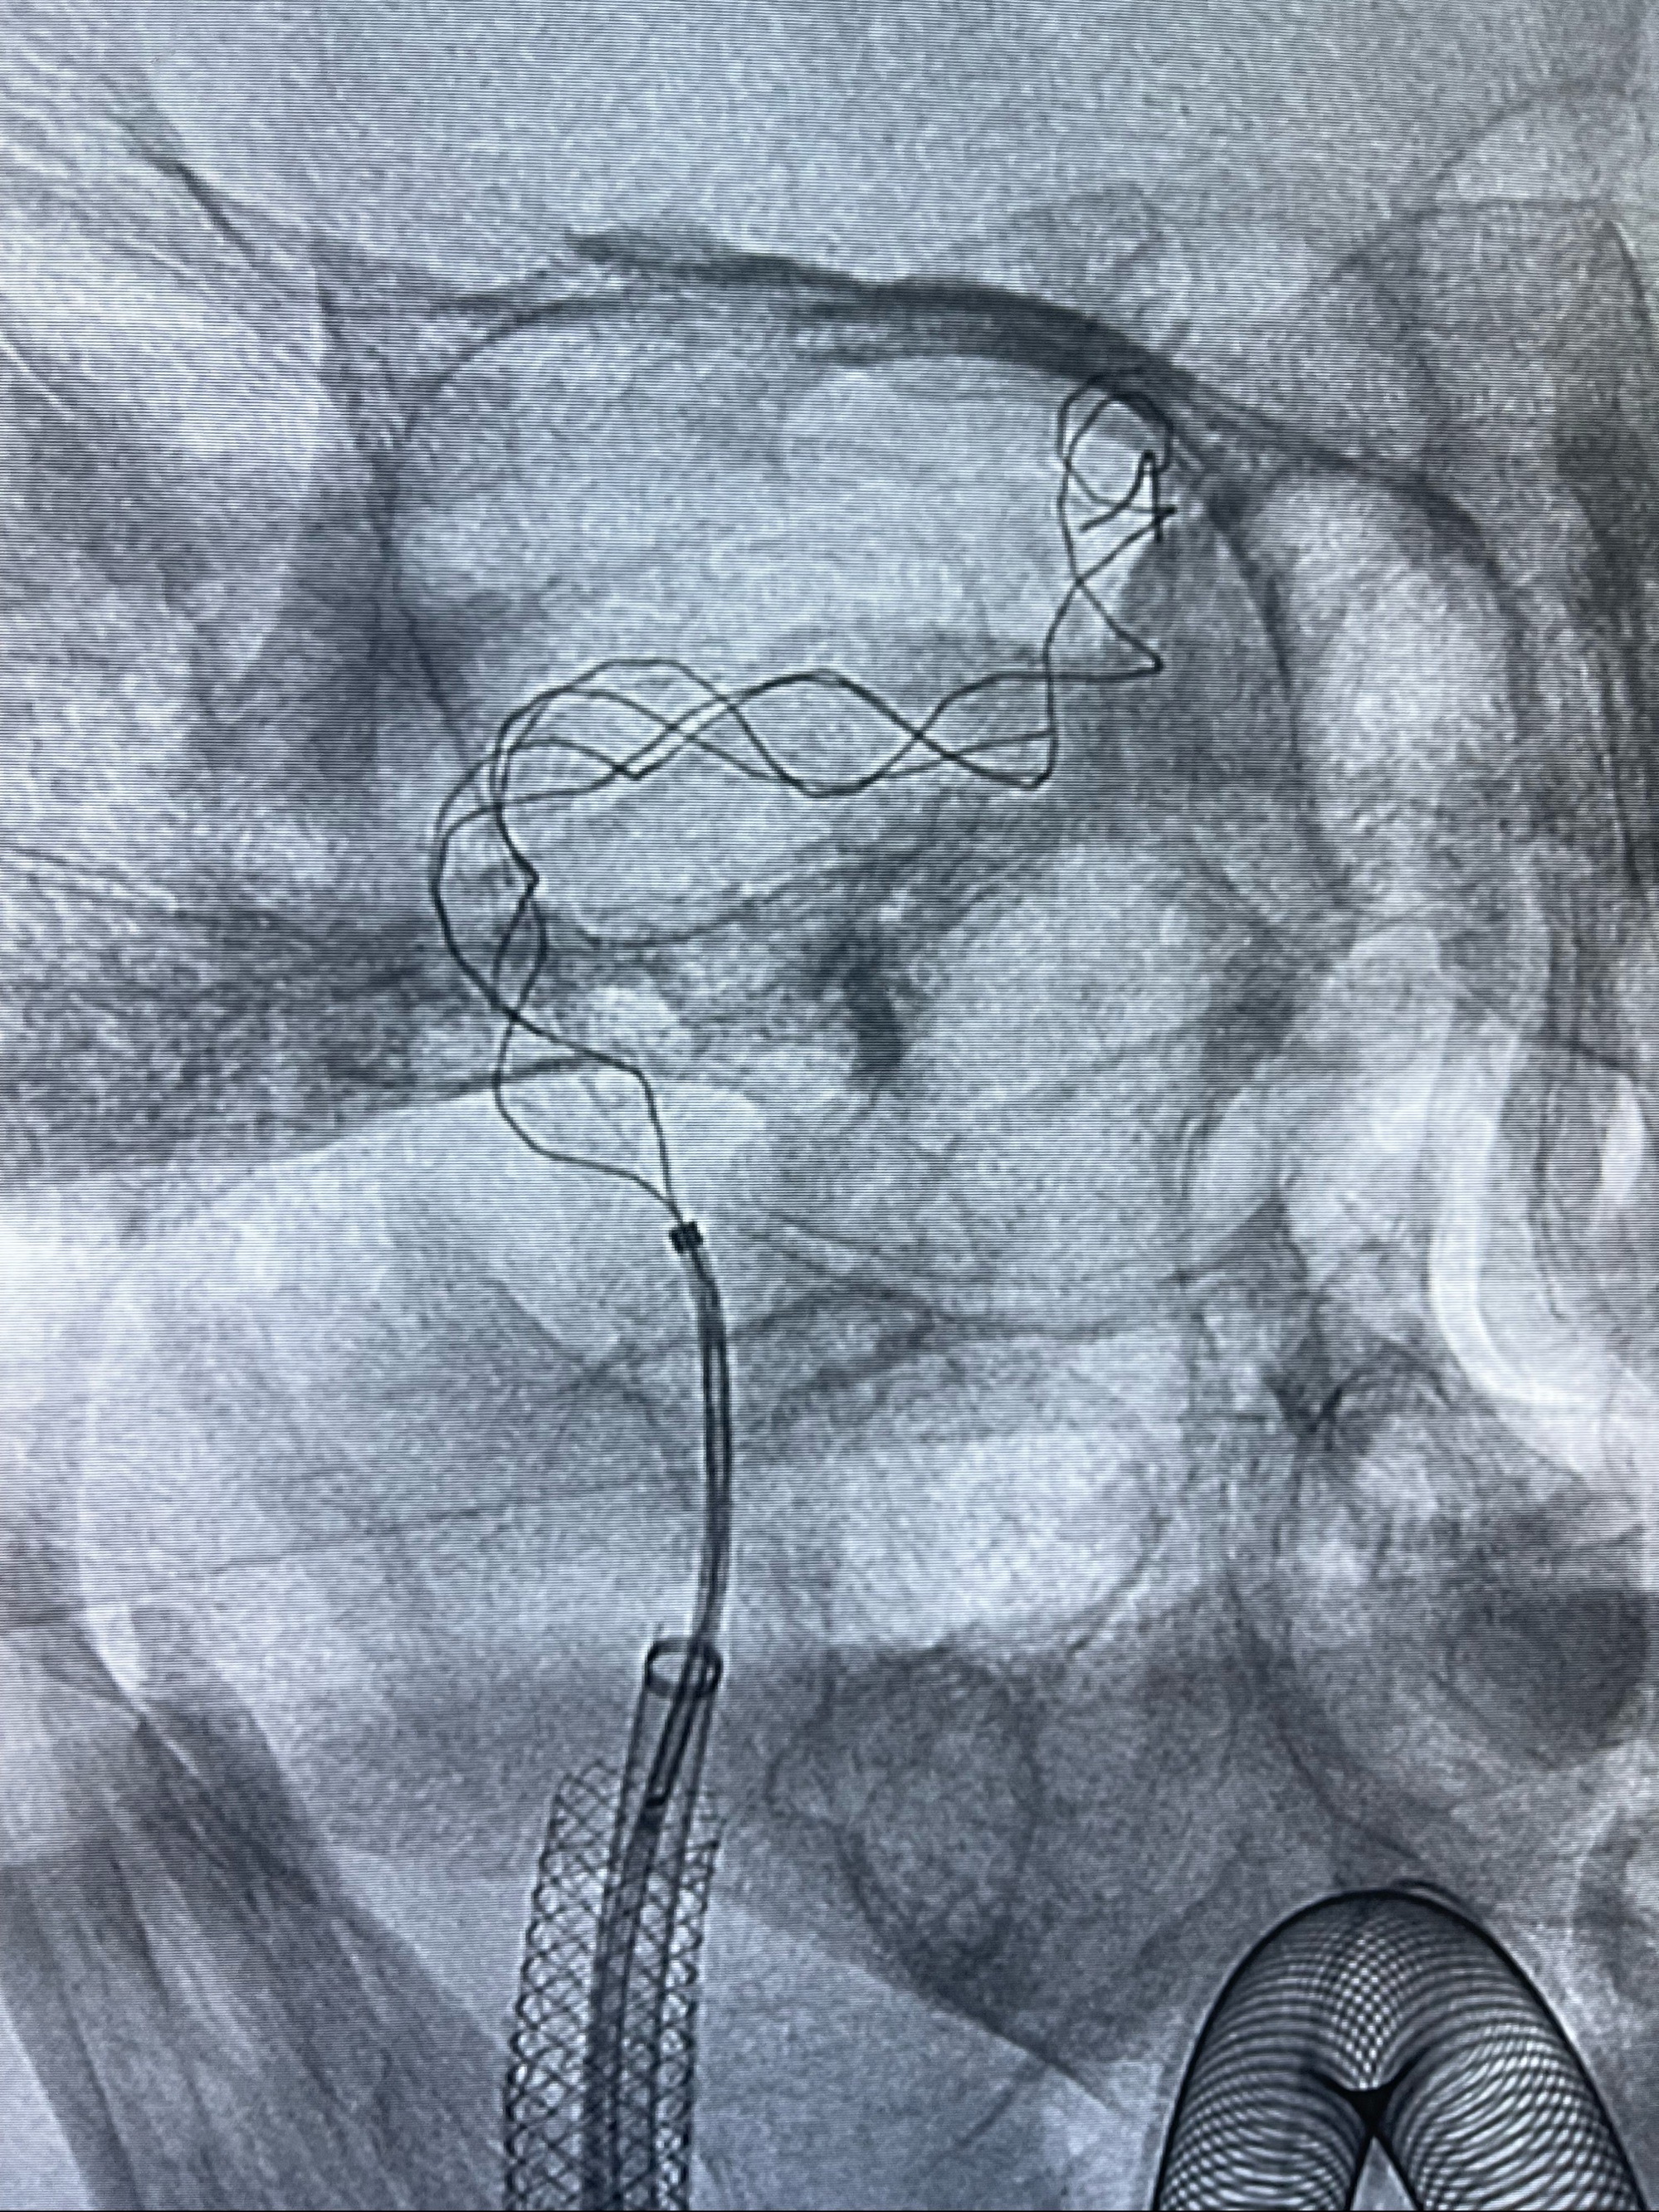

双抗准备后于2023-07-13在全麻下行右侧颈内动脉功能保护

088NeuroMAX100cm长鞘在125cmMPA及黑泥鳅导丝引导下超选择性插入右侧颈内动脉支架内

经导引导管造影显示支架远端颈内动脉不规则狭窄伴局部充盈缺损,同时行全身肝素化5ml

路径图下4-20mm球囊在导丝引导下超选择性至狭窄段,以6-8个大气压扩张,持续30s

泄除球囊造影显示局部管腔扩张佳

后移球囊至颈段狭窄段,以8-12个大气压扩张,持续30s后泄除球囊

即刻造影显示狭窄扩张佳

重新行“路径图”,支架导管在微导丝引导下超选择性插入至右侧颈内动脉眼段,4.5-50mmLeo支架释放,远心端位于海绵窦段,近心端位于岩骨段狭窄段以近

即刻造影显示支架贴壁佳

路径图下,5.5-50mmLeo支架导管在微导丝引导下超选择性插入远段Leo支架内

两枚支架部分重叠

多次确认支架位置及打开贴壁情况

支架完全打开,近心端位于原颈动脉支架远心端内